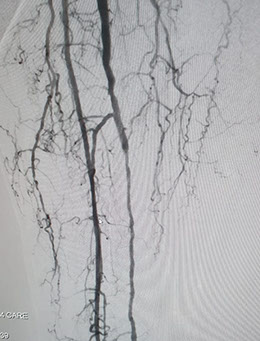

Las imágenes siguientes son previas al procedimiento y posterior se ve ambas arterias tíbiales permeables, y circulación en el pie